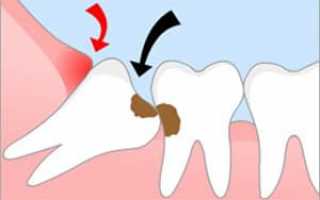

Медиальный наклон часто приводит к развитию кариеса в соседней семёрке из-за разрушения эмали и накопления остатков пищи в щели между верхушками. Щёчный наклон часто сопровождается травмированием слизистой щеки, что может привести к образованию опухоли. При дистальном наклоне требуется удаление зуба мудрости.

Также существует воспалительное заболевание, называемое перикоронитом, которое возникает при длительном прорезывании верхушки зуба мудрости. При этом зуб мудрости может прорезываться в течение года или даже нескольких лет. В результате травмирования десны появляется «кармашек», в котором скапливаются остатки пищи и развивается воспаление.